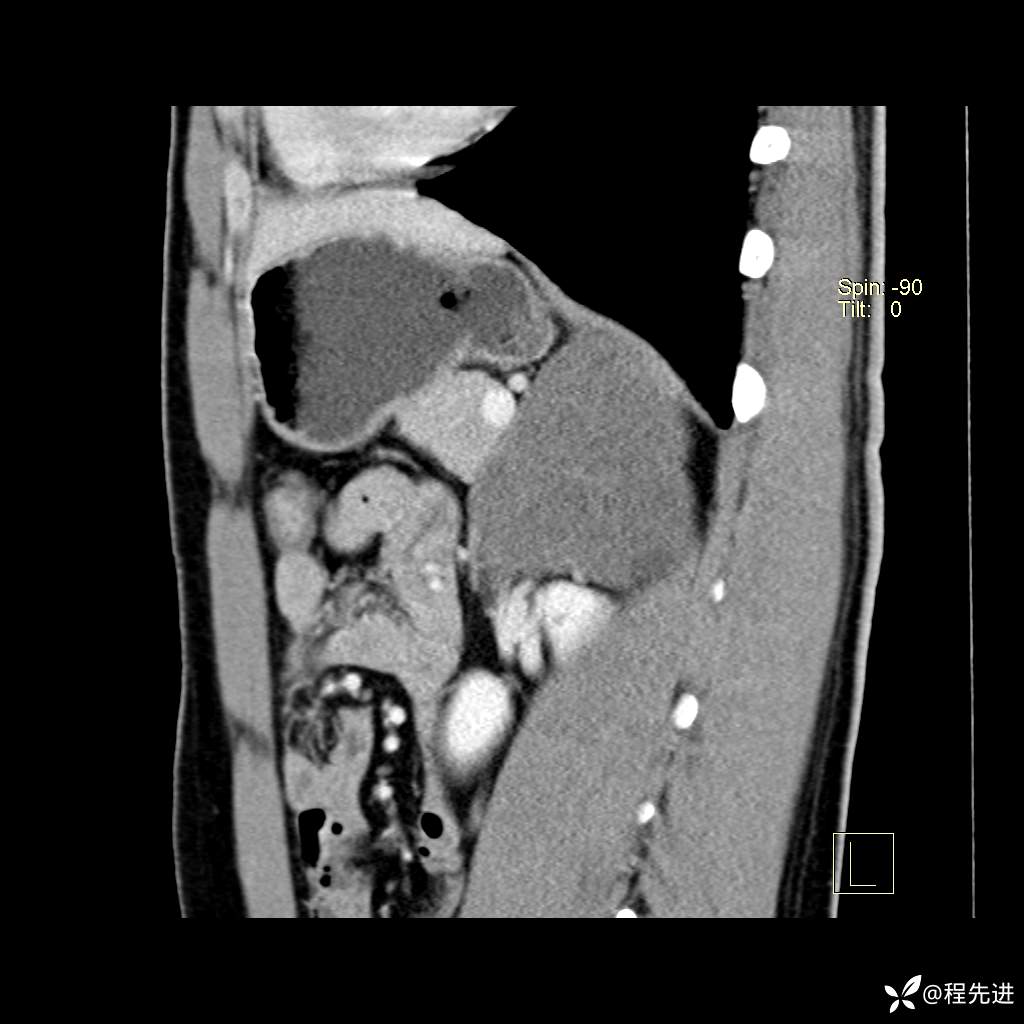

矢状位重建: